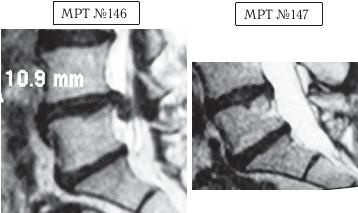

Ещё один довольно тяжёлый случай. Однако, как говорят врачи, пациент и врач предполагают, а природа располагает. Здесь также было достаточно одного курса лечения.

На МРТ №146 в поясничном отделе позвоночника наблюдается секвестрированная грыжа межпозвонкового диска в сегменте LIV-LV с разрывом задней продольной связки.

На МРТ № 147 наблюдается результат после одного курса лечения методом вертеброревитологии.